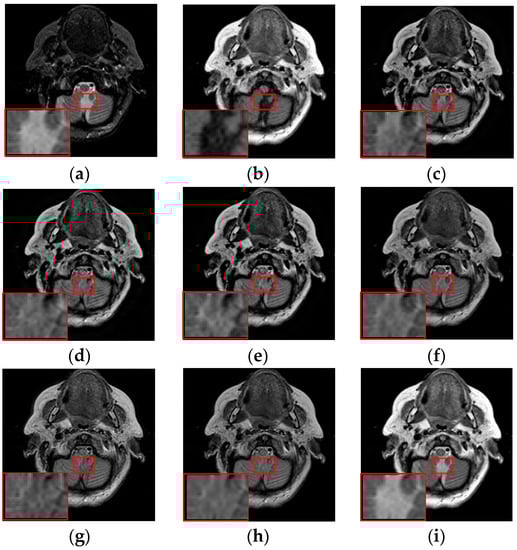

To further demonstrate that the proposed method is equally effective for other types of medical image fusion, we test the other two categories of medical image fusion systems include MRI/SPECT and MRI/PET, and the fusion results are shown in Figure 9 and Figure 10. The details of fused images are zoomed in and presented in the bottom left corners of their respective images.

Figure 9.

Fused results of MRI/SPECT medical images by different methods. (a) MRI; (b) SPECT; (c) DCTWT; (d) Curvelet; (e) NSCT; (f) Liu-ASR; (g) Kim; (h) Zhu; (i) Proposed.

Figure 10.

Fused results of MRI/PET medical images by different methods. (a) MRI; (b) PET; (c) DCTWT; (d) Curvelet; (e) NSCT; (f) Liu-ASR; (g) Kim; (h) Zhu; (i) Proposed.

With more careful observation, we can see that the spatial edge details and brightness information in Figure 9i and Figure 10i are more accurate compared with Figure 9c–h and Figure 10c–h generated by the six compared methods. This means the useful information from source images have been successfully transformed into the fused images, that is, our fused results have the best visual features. This is mainly because the novel construction of the overcomplete dictionary in this paper is composed of two parts include the brightness sub-dictionary and the edge detail sub-dictionary, which can fully express the significant features of the medical images. This will be very beneficial to the implementation of medical image fusion in practical medical assistance applications. In conclusion, the proposed algorithm has the best subjective visual effect.